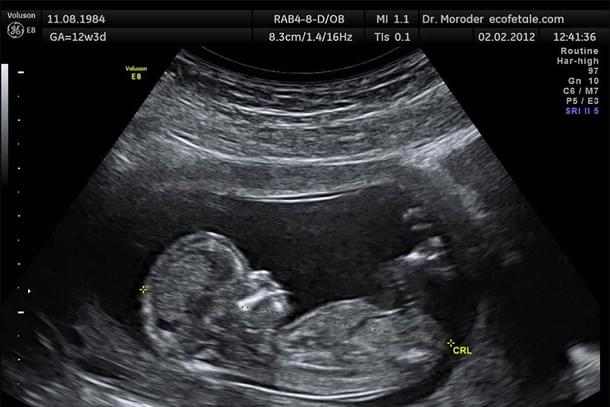

Brief Recap: On Monday, Politico published a leaked draft opinion of the US Supreme Court that indicated it would strike down Roe v. Wade. This would leave abortion legislation to individual states and make it harder for Americans to make life and death decisions on behalf of the unborn child. The decision of life and death is the most significant decision. Due to the unborn child's vulnerability, the unborn child has very little protection if the unborn child's mother herself decides that this life form must never see the world outside the womb as it would hinder the mother's priorities.

A basic grasp of science without being coloured by lens of ideology would reveal that the unborn child develops heartbeat as early as week 5 and the unborn child's electrical brain activity can be detected as early as week 6. Of course the brain isn't fully developed yet, but the human brain actually takes quite a long time to develop. In fact until the age of 24, the brain's prefrontal cortex isn't fully developed. Surely we all have come across people who make us wonder if even after age of 24 it is fully developed.